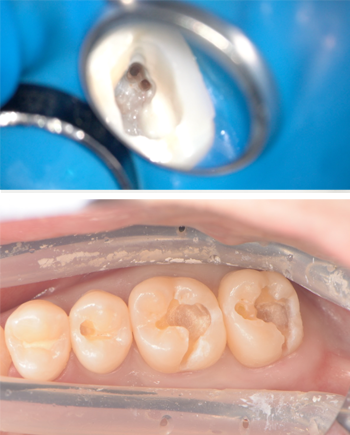

唾液の侵入を防ぐラバーダムやZOOを常に使用

歯科治療において「唾液は大敵」です。

唾液の中には細菌が大量に存在するため、根管内に流入をさせてしまうと内部に新たな感染を引き起こしてしまいます。

それを防ぐためにラバーダム(青いゴムのシート)は必須です。

修復物を歯に接着させる際にも、唾液が歯の表面に付着していると歯と修復物の接着が阻害されます。

当院では接着操作を行う際には必ずZOO(唾液を吸引するホース状の器具)を用いて唾液の排除を徹底しております。